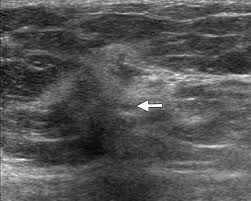

Did not respond to antibiotic and was referred for biopsy. Inflammatory breast cancer is often misdiagnosed because it is so rare, and is difficult to treat because it is particularly aggressive. What does breast cancer look like on a mammogram? However, inflammatory breast cancers are more likely to show solid mass lesions. My last breast ultrasound was december. As these inflammatory breast cancer picture shows, the texture of the breast may change and appear to look dimpled or ridged, like an orange peel. The woman who has inflammatory breast cancer has breast cancer that's red and inflamed, with an angry look to the breast cancer, he says. The problem is that inflammatory breast cancer can look very much like mastitis early on, and is often diagnosed only after a woman has been treated first for mastitis (often with no improvement in symptoms). What does breast cancer look like? I need some knowledge about ibc. These tubes, which are hollow, allow lymph fluid to drain out of the breast. I have inflammatory breast cancer which was firstly diagnosed as mastitis in jan 09. Women or men who develop any of the inflammatory breast cancer early signs should seek medical care immediately to ensure timely treatment.

The woman who has inflammatory breast cancer has breast cancer that's red and inflamed, with an angry look to the breast cancer, he says. What does breast cancer look like? Googled and freaking out about ibc. The problem is that inflammatory breast cancer can look very much like mastitis early on, and is often diagnosed only after a woman has been treated first for mastitis (often with no improvement in symptoms). Mammogram imaging may show skin thickening, but often there is no distinct mass found on physical examination or …

It's called inflammatory because that's how it looks. Any area that does not look like normal tissue is a possible cause for concern. Inflammatory breast cancer, also known as carcinomatous mastitis, t4d, or pev 2 or 3, is the only real therapeutic emergency in breast oncology, given the high risk of metastasis, the reason for the most unfavourable prognosis of all breast cancers.it must consequently be diagnosed rapidly, and imaging examinations must in no case delay therapeutic management. Because ibc grows quickly, it is usually found at a locally advanced stage, meaning that cancer cells have spread into nearby breast tissue or lymph nodes. A breast ultrasound is a scan that uses penetrating sound waves that do not affect or damage the tissue and cannot be heard by humans. Ultrasound is useful for looking at some breast changes, such as lumps (especially those that can be felt but not seen on a mammogram) or changes in women with dense breast tissue. As these inflammatory breast cancer picture shows, the texture of the breast may change and appear to look dimpled or ridged, like an orange peel. Their differences, however, lie in their enhancement.

These tubes, which are hollow, allow lymph fluid to drain out of the breast. The problem is that inflammatory breast cancer can look very much like mastitis early on, and is often diagnosed only after a woman has been treated first for mastitis (often with no improvement in symptoms). Kathleen ruddy inflammatory breast cancer accounts for approximately 5% of all cases of invasive breast cancer in the united states. Inflammatory breast cancer is often misdiagnosed because it is so rare, and is difficult to treat because it is particularly aggressive. A small red spot that looks very much like an insect bite or rash can be an early sign of ibc. Because ibc grows quickly, it is usually found at a locally advanced stage, meaning that cancer cells have spread into nearby breast tissue or lymph nodes. Googled and freaking out about ibc. The woman who has inflammatory breast cancer has breast cancer that's red and inflamed, with an angry look to the breast cancer, he says. Online says it develops suddenly. However, these signs and symptoms are most often associated with benign breast conditions. Inflammatory breast cancer (ibc) is rare, making up about 2 to 4 percent of breast cancer cases. Other ultrasound findings that suggest breast cancer include: The breast tissue deflects these waves causing echoes, which a computer uses to paint a picture of what's going on inside the breast tissue (no radiation is involved).